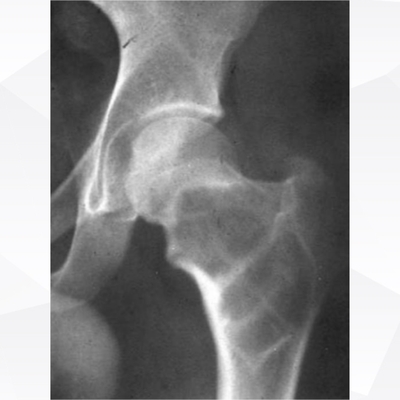

Click on an image below to view more info.